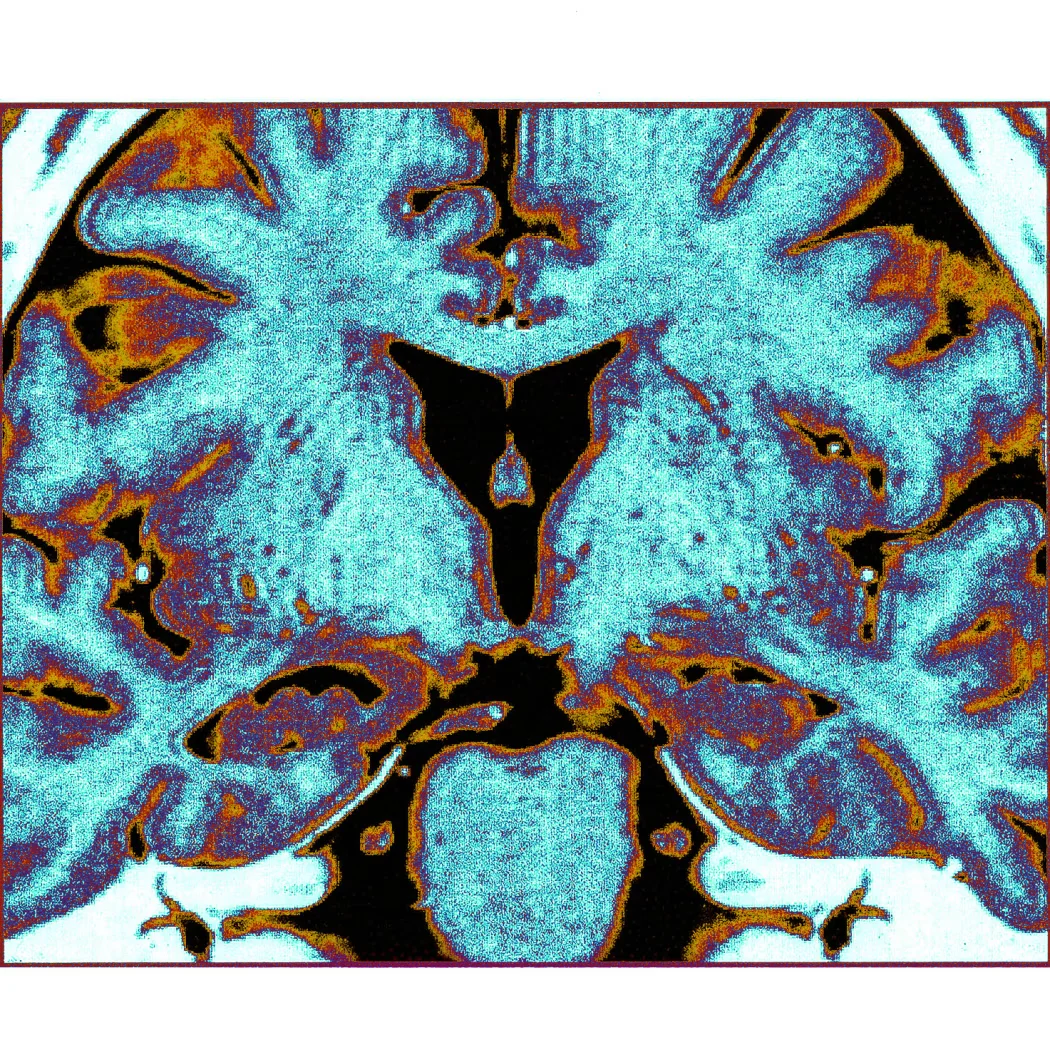

Одна з найсміливіших мрій науки — зберегти живий мозок у замерзлому стані й повернути його до повноцінної роботи — зробила безпрецедентний крок уперед. Як повідомляє Wall Street Journal, дослідникам із Університету Ерлангена–Нюрнберга вдалося заморозити зрізи гіпокампу мишей до −196°C, зберігати їх до семи днів і після розморожування відновити електричну активність нейронів та механізм довгострокової потенціації — клітинну основу навчання і пам’яті. Це перший у світі задокументований випадок, коли доросла ссавецька мозкова тканина відновила настільки складні функції після повного кріогенного заморожування.

- Зрізи гіпокампу мишей завтовшки 350 мікрометрів (утричі тонша за людський волос) оброблялися кріопротекторним розчином, а потім охолоджувалися до −196°C за допомогою рідкого азоту та зберігалися при −150°C.

Після відтавання у теплих розчинах тканину ретельно аналізували. Мікроскопія виявила збережені мембрани нейронів і синапсів. Електрофізіологічні записи показали, що нейрони відповідали на електричні стимули близько до норми — з помірними, але прийнятними відхиленнями. Найголовніше: довгострокова потенціація (LTP) — те саме явище зміцнення синаптичних зв’язків, яке вчені пов’язують із формуванням спогадів — залишалася функціональною. Це означає, що клітинний механізм навчання і пам’яті не було зруйновано заморожуванням.

Важливо розуміти, що саме відбулося — і чого не відбулося. Дослідники не відновили живу мишу після заморожування. Не довели збереження свідомості чи особистості. Не показали, що мозок цілком може пережити кріоніку. Те, що їм вдалося — відновити базові електрофізіологічні та метаболічні функції невеликих зрізів гіпокампу, включаючи LTP. Гіпокамп є ключовою структурою для просторової навігації і формування спогадів — саме він першим страждає при хворобі Альцгеймера.